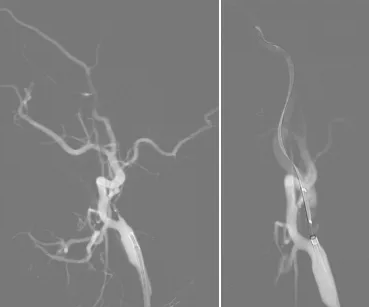

汉中市中心医院高级卒中中心成功救治一例外地在汉旅游危重卒中患者

健康生态

2024年6月5日